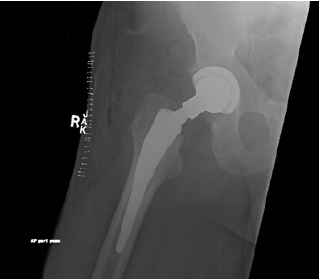

Serum creatinine was 1.02mg/dL. BUN was 19mg/dL. AST was 37U/L, and ALT was 40U/L. Urinalysis revealed: 0-2 RBCs, 0-2 white blood cells and no proteinuria. ESR was 36mm/h. Rheumatoid factor was < 10 IU/mL. ANA was negative. Due to the severe symptoms and the MRI findings of subcortical fracture of the right hip, the patient underwent right total hip replacement (Figure 4). He was treated with a short course of prednisone 0.5mg / kg on a tapered dosing regimen for 1 month after the hip replacement. This regimen helped to resolve his skin lesions. However, the patient experienced a relapse of the skin lesions 1 week following the discontinuation of his prednisone regimen. He was treated with another course of 0.5mg / kg with the addition of methotrexate 15 mg weekly. The new regimen was adequate to resolve his skin lesions.